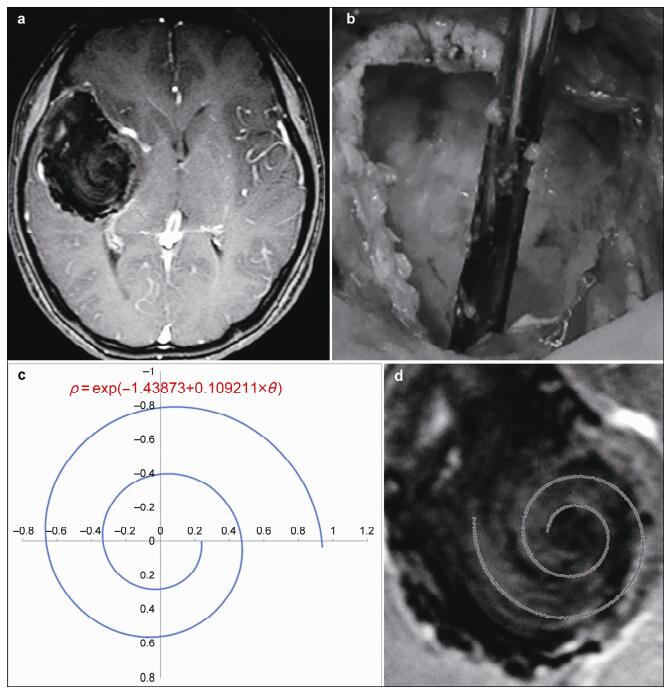

20170308102244  Figure 1 a. Image of the intracranial dermoid cyst. Magnetic resonance imaging revealed a 4-cm lesion with isointense or hypointense mixed signals on T1-weighted images and scanty enhancement after gadolinium injection. b. Tumor contents with an appearance like egg-drop soup. c. Graphical representation of the equation describing the spiral pattern in the cyst. d. Merged image of the calculated spiral curve and spiral seen in the tumor demonstrating a good fit.

摘要 A logarithmic spiral is a self-similar spiral curve, which often appears in nature, e.g., mollusk shells. In the normal tissues of the human body, the cochlea is also an approximate logarithmic spiral. However, approximate logarithmic spirals are rarely, if ever, reported in tumors. Recently, we treated a 26-year-old woman with a one-year history of headache. Preoperative magnetic resonance imaging showed a possible brain tumor with radiological characteristics similar to a typical logarithmic spiral, which has seldom been observed before. Because of the obvious clinical symptoms and discomfort, as well as the possible presence of an intracranial tumor, we performed a craniotomy and tumor resection. Perioperatively, we found an intact tumor capsule, with contents that appeared like egg-drop soup mixed with hairs. A post-operative pathological diagnosis of a dermoid cyst was made. However, more interestingly, the logarithmic spiral could be described mathematically with a high goodness of fit. In this paper, we present this case with various clinical images.

Abstract: A logarithmic spiral is a self-similar spiral curve, which often appears in nature, e.g., mollusk shells. In the normal tissues of the human body, the cochlea is also an approximate logarithmic spiral. However, approximate logarithmic spirals are rarely, if ever, reported in tumors. Recently, we treated a 26-year-old woman with a one-year history of headache. Preoperative magnetic resonance imaging showed a possible brain tumor with radiological characteristics similar to a typical logarithmic spiral, which has seldom been observed before. Because of the obvious clinical symptoms and discomfort, as well as the possible presence of an intracranial tumor, we performed a craniotomy and tumor resection. Perioperatively, we found an intact tumor capsule, with contents that appeared like egg-drop soup mixed with hairs. A post-operative pathological diagnosis of a dermoid cyst was made. However, more interestingly, the logarithmic spiral could be described mathematically with a high goodness of fit. In this paper, we present this case with various clinical images.